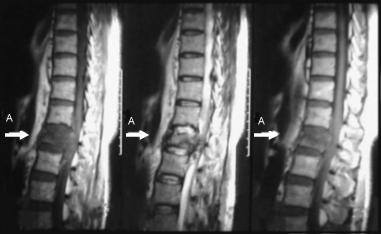

Corte sagital

Flecha: Observe la fractura del cuerpo vertebral L1, con escaso compromiso del canal medular.